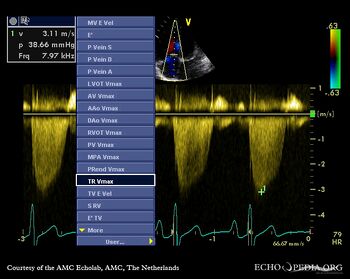

| Continuous-wave Doppler signal of transmitral flow

Continuous-wave Doppler signal of transmitral flow: PHT 117 msec

| Continuous-wave Doppler signal of tricuspid regurgitation: pulmonary hypertension